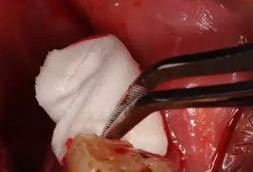

8.處理拔牙窩

使用生理鹽水對(duì)拔牙窩進(jìn)行清洗和(或)用強(qiáng)吸方法徹底清理碎片,可用刮匙刮除粘連軟組織的碎片,但不能過(guò)度搔刮牙槽窩,以免影響愈合。對(duì)于肉芽組織,如探查為脆弱松軟、易出血的炎性肉芽組織,應(yīng)予以刮除;如探查為韌性、致密的纖維結(jié)締組織,則對(duì)愈合有利,不必刮除。應(yīng)去除包繞牙冠的牙囊,以免形成殘余囊腫。壓迫復(fù)位擴(kuò)大的牙槽窩,修整銳利骨緣,取出游離折斷骨片。為預(yù)防出血,可在拔牙窩內(nèi)放入膠質(zhì)海綿1~2塊。